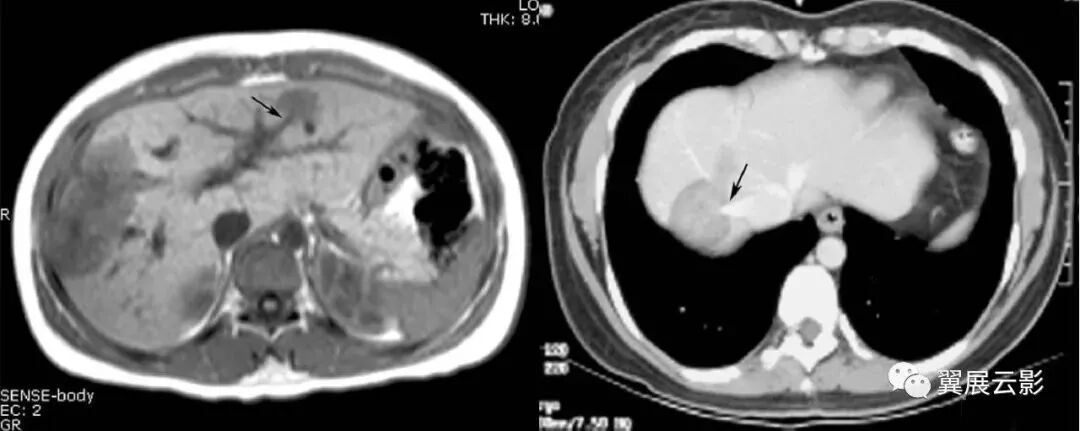

图1,2 肠系膜脂膜炎。

图1 为 MSCT平扫,显示肠系膜密度增高,CT值为 – 47 HU,与腹腔正常脂肪有清楚分界 (箭头) ,且显示肠系膜血管(箭)周围无受累,呈“脂肪环征”。

图2 为MSCT门静脉期,显示肠系膜无明显强化,CT值为 – 45 HU,与腹腔脂肪有清楚界限,形成假包膜征 (箭头) ,邻近肠管有推移改变。